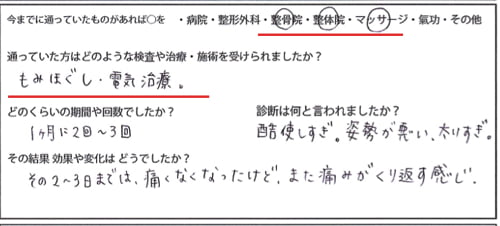

今までの治療履歴は整骨院・整骨院・マッサージなどで

もみほぐし 電気治療などでしたが、すぐに痛みがぶり返す感じでした。